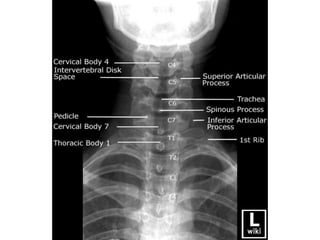

Radiographic Signs of Trauma

Alignment

disrupted cervical arcs

Focal kyphosis/scoliosis/loss of lordosis

Spinous process rotation

Vertebral listhesis

Cartilage (joint/disc) space

facet widening

Interspinous widening (ā€œfanningā€)

Widened predental space

Widened/narrowed disc space

Bone Integrity

fracture/cortical buckling

Disrupted posterior vertebral body line

Anterior wedging

Disrupted C2 ring (ā€œfatā€ C2 sign)

Soft Tissue

widened prevertebral space

Displaced prevertebral ā€œfatā€ strip

Vacuum disc phenomenon

Deviated airway